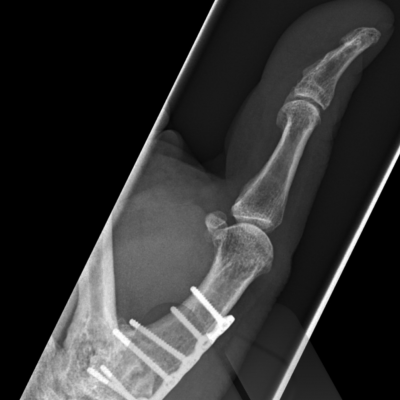

Excisional arthroplasty and interposition

This is where a bone is removed to create space to unload the cartilage surface, to relieve pain and maintain movement. These techniques have been used since the 1950’s and 60’s in various joints in the hand.

Joint replacement

Joint replacements can use many types of materials including silicone, metal and plastic and pyrocarbon. Silicone joint replacements have been used in the small joints of the hand since the early 1960’s. They have a long track record and have a predictable outcome and ability to exchange implants if they fail. Modern day Metal on plastic implants have evolved since 1979 and now resemble modern day “mini knee replacements”. Pyrocarbon is a newer material and has been used since 2000. It can be implanted as a total joint replacement or hemiarthroplasty (replacing only one damaged side of the joint). Most joint replacement surgeries provide good relief of pain whilst maintaining motion however it is difficult to reliably improve range of motion in very stiff fingers.